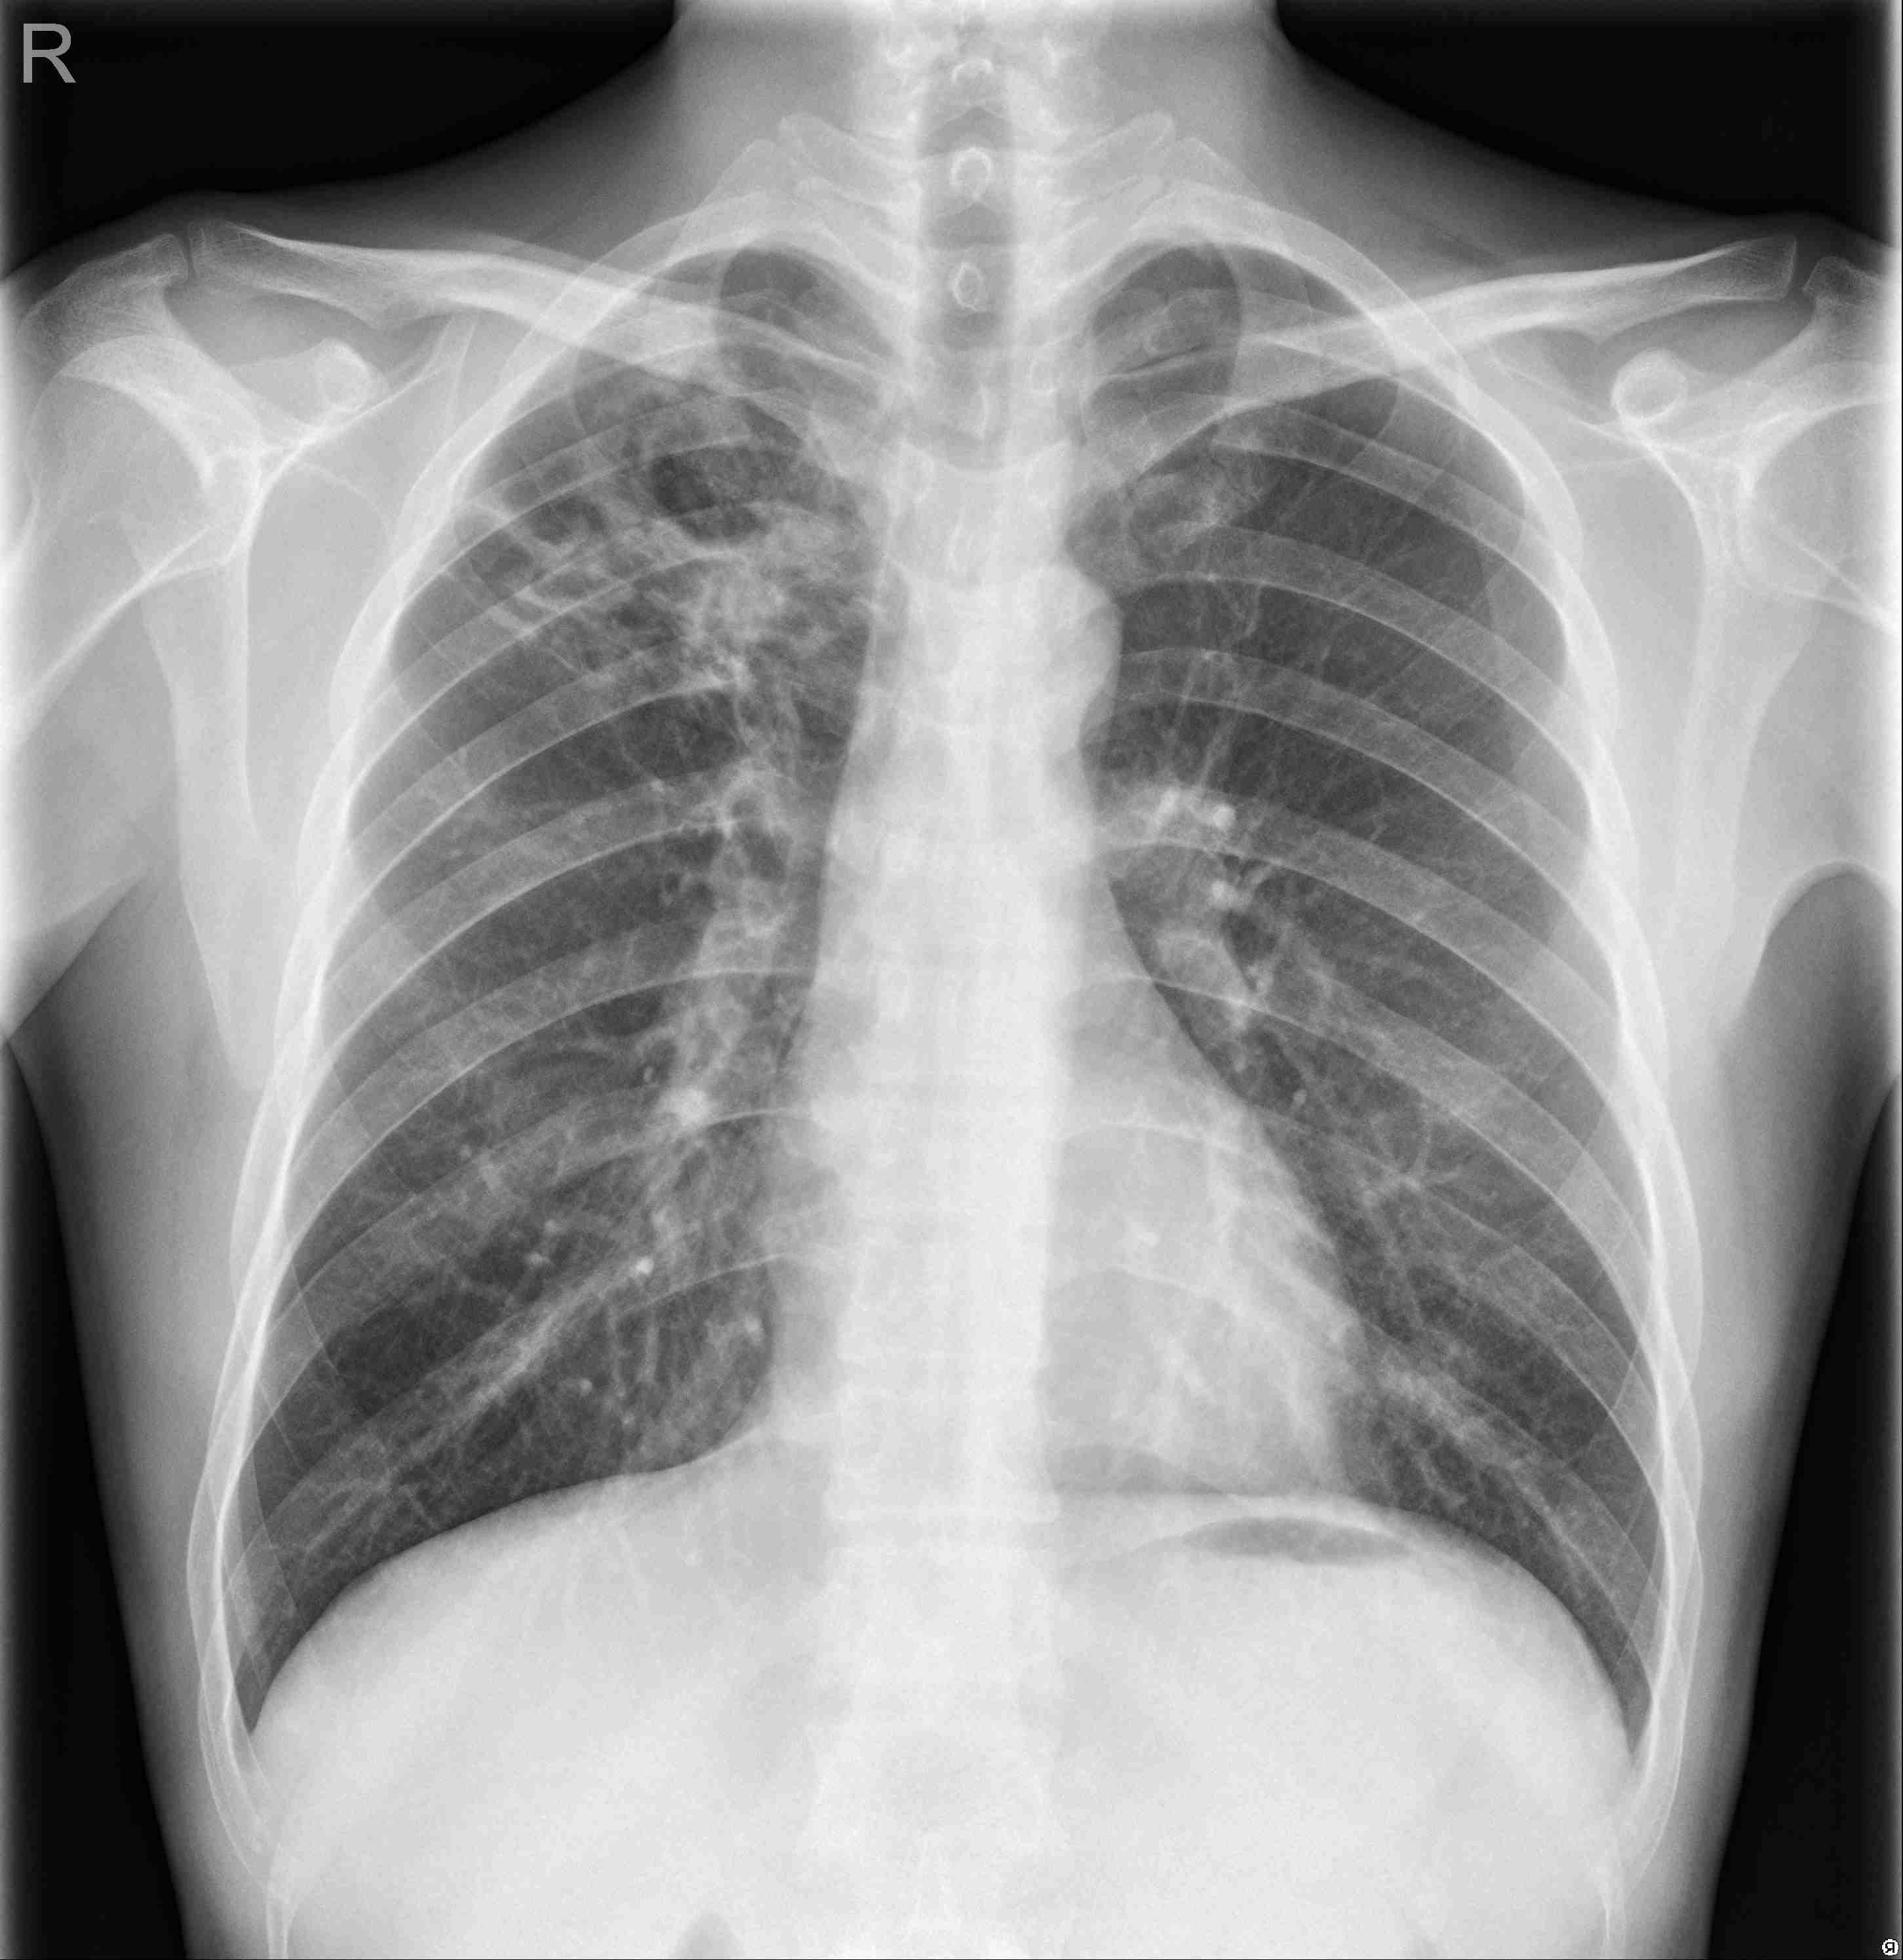

Tuberculosis Analyzer

Results